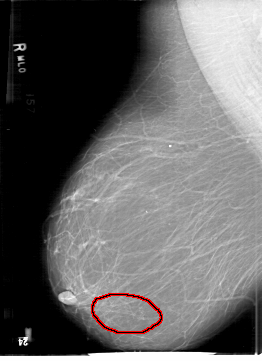

D_4190_1.RIGHT_MLO

FILE: D_4190_1.RIGHT_MLO.OVERLAY

TOTAL_ABNORMALITIES 1

ABNORMALITY 1

LESION_TYPE CALCIFICATION TYPE FINE_LINEAR_BRANCHING DISTRIBUTION CLUSTERED

ASSESSMENT 0

SUBTLETY 4

PATHOLOGY MALIGNANT

TOTAL_OUTLINES 1

BOUNDARY